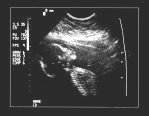

Ultrasound is a way of taking a look at the baby without using potentially dangerous X-rays. During an ultrasound scan, high-frequency soundwaves are used to create moving images of the developing baby, shown on a screen.

When you have a pregnancy ultrasound, a type of gel is spread on your abdomen and a device that produces and receives soundwaves (a transducer) is moved over your skin. The soundwaves ‘bounce’ off the baby and other internal structures, creating pictures on a TV screen.

The sonographer (the health professional performing the ultrasound scan) may show you some of the images of your baby on the screen, and may also print some of the images for you. The images will also be reviewed by a radiologist (specialist in medical imaging) and your obstetrician or midwife.